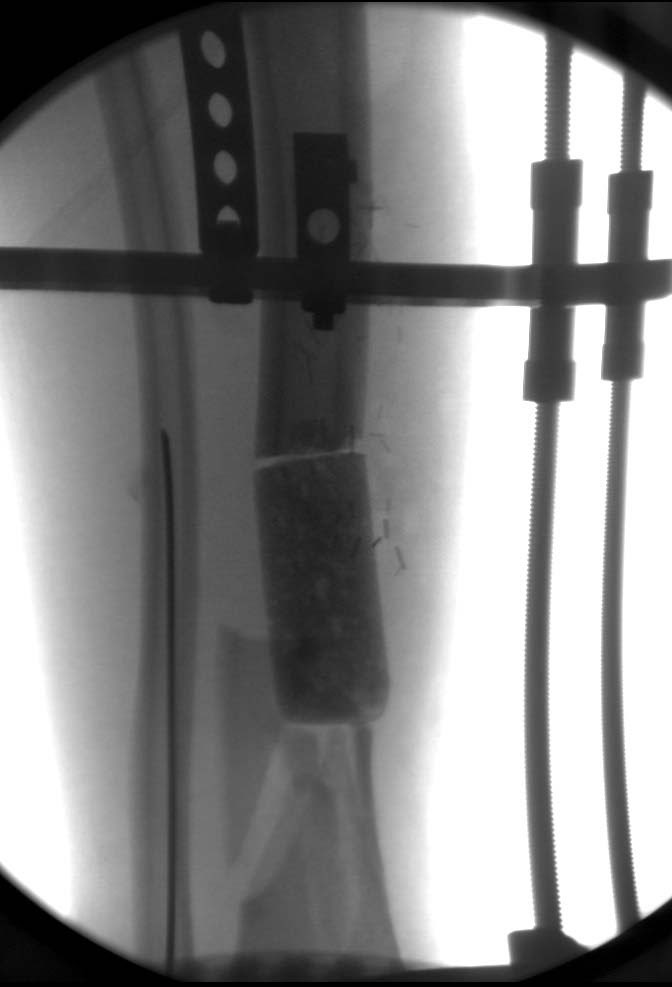

Данный случай не огнестрельная рана, а результат мотоциклетной аварии.

Независимо от повреждения при таких обширных дефектах мягких и костной

тканей применяется схожая тактика. Как видно, после нескольких I&D для

создания “pseudo membrane” применили цилиндрический блок из цемента.

Дефект мягких тканей закрыли свободным Anterior Thigh Graft. Из малого

доступа цилиндр удален небольшими кусочками, а пространство заполнили

бусами для освобождения пространства. По мере приближения регенерата

освободили пространство удалением бус через небольшой разрез. Этап

созревание регенерата можно было ускорить усилением интрамедуллярным

гвоздем, но решили закончить методом Илизарова.